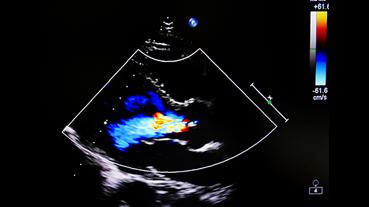

In 2025, cardiologists and cardiac surgeons at NewYork-Presbyterian led breakthroughs that impacted a range of diseases and conditions from advanced heart failure to pediatric valve disease. Physicians and researchers from Columbia and Weill Cornell Medicine pioneered the use of artificial intelligence to identify structural heart disease, launched a mobile app to expand access to heart failure education, performed one of the first split-root domino partial heart transplants, and more. Our experts remained at the forefront of innovative, multidisciplinary care, delivering comprehensive treatment for the most complex cardiac diseases.

Our world-renowned Columbia and Weill Cornell Medicine physicians and surgeons in our comprehensive cardiology, heart surgery, and vascular programs spearhead groundbreaking clinical and scientific research and provide the most innovative treatments to optimize patient outcomes for all stages of disease complexity. Our clinicians are experts in minimally invasive approaches and novel therapeutics for all types of heart disease and work across disciplines to provide compassionate care to all patients.